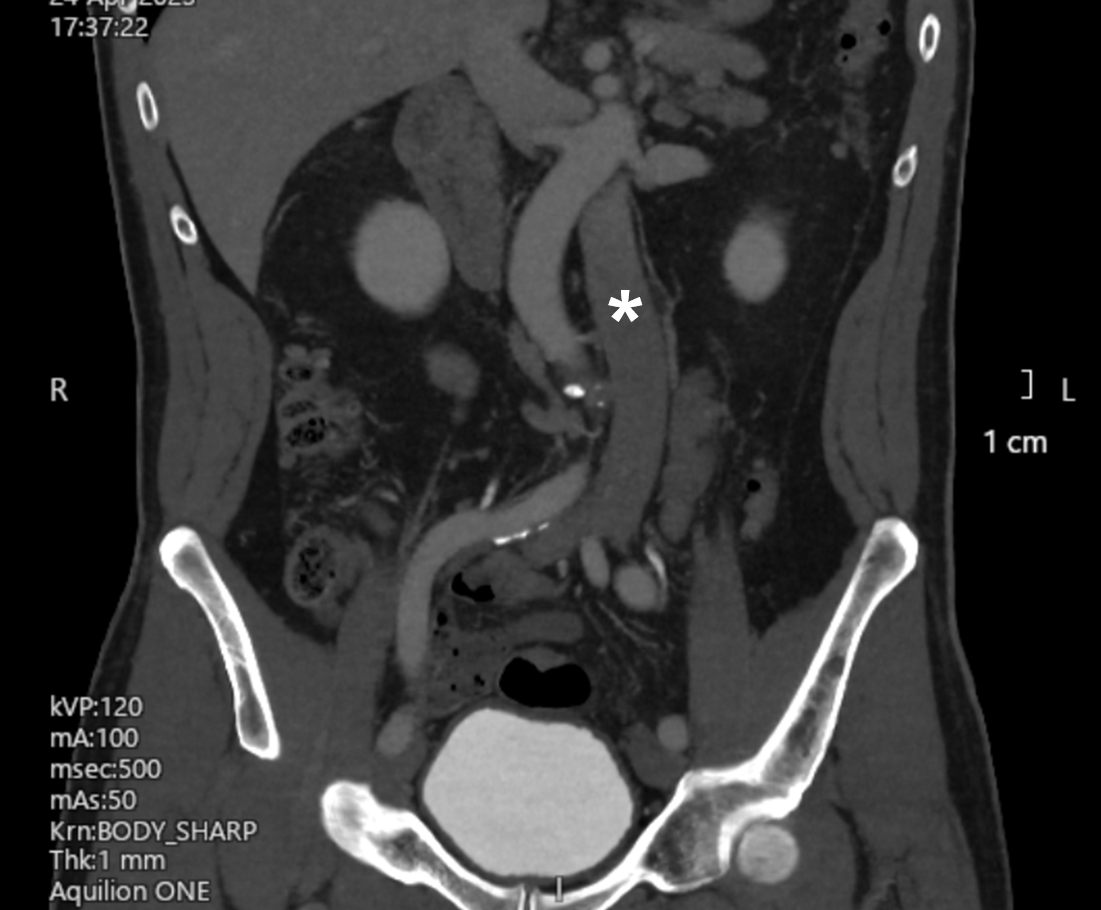

A computed tomography (CT) venogram of the inferior vena cava (IVC) and iliac and femoral veins was arranged. The scan showed a left-sided IVC, which “crossed over” to the right side at the renal vein level (Figure 2). The apparent filling defect was attributable to external compression of the right common iliac vein by the left iliac artery as it crossed to the left side (Figure 3).

Figure 2. (A-C) Three consecutive cuts of coronal plane images (anterior to posterior) from the patient’s computed tomography venogram. The left-sided inferior vena cava is marked with an asterisk. (B) The right iliac vein appeared to be compressed by the left iliac artery (arrow), which may explain the intraprocedural finding.